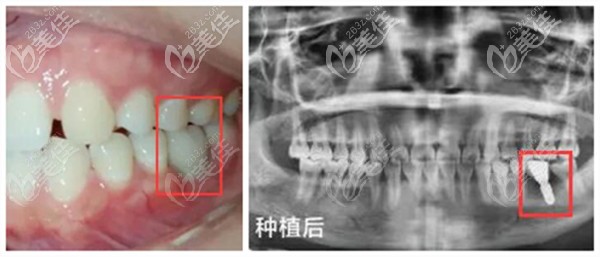

即刻種植技術(shù):在拔牙后即刻植入種植體、安裝基臺、牙冠,當(dāng)天就可以恢復(fù)咬合功能;不用像傳統(tǒng)種植牙一樣等3-6個月,也不用做二次手術(shù)。

微創(chuàng)種植技術(shù):手術(shù)創(chuàng)傷小,只有3MM左右,種一顆牙只需10分鐘左右即可完成。